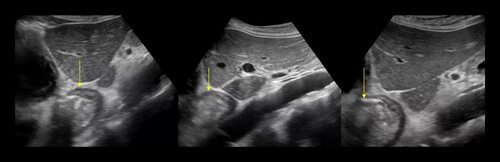

Грыжа является серьезной проблемой, которая может возникнуть у женщин. Для более точного диагноза и визуализации данного заболевания, врачи часто используют ультразвуковое исследование (УЗИ). Благодаря УЗИ, можно увидеть грыжу на фотографии внутри тела пациента.

Фото грыжи у женщин, полученные при помощи УЗИ

На фотографиях, сделанных при помощи УЗИ, можно увидеть грыжу и ее характеристики. Это позволяет врачам более точно определить размер и местоположение грыжи внутри организма. Фото УЗИ являются важным инструментом для правильной диагностики и планирования лечения у женщин, страдающих от грыжи.